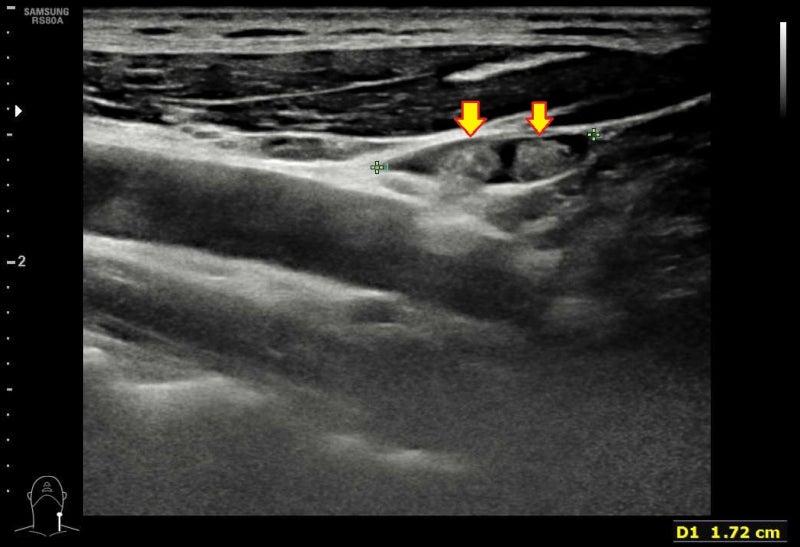

갑상선에 결절이 발견되면 옆 경부 림프절까지 잘 관찰해야 암 진단에도 도움이 되고 수술 범위를 정하는 데도 도움이 됩니다. 그런데 일반적으로 갑상선 암의 진단 환자도 옆 경부 림프절 검사를 게을리하는 일이 많습니다. 다른 병원에서 검사한 뒤 생큐 서울 이비인후과를 찾은 환자(712명)의 초음파 사진을 다시 검토한 결과 66%의 환자의 초음파 검사 사진에서 측 경부 검사가 빠지고 있었습니다.대학 병원 가운데 빅 5도 22%에서 탈락하며 빅 5를 제외한 대학 병원은 48%에서 탈락했어요.샌 환자들을 고마워서울 이비인후과에서 초음파 검사를 했는데, 약 6%의 환자에게서 측 경부 림프절 전이가 발견되었습니다.(해당 내용은 최근 대한 갑상샘 학회에서 발표했습니다.)관련의 증례를 하나 소개합니다.30세 남자 환자가 2년 전으로 건드리는 갑상선 결절에 대해서 상담하기 위해서, 생큐 서울 이비인후과- 내분비 내과 이·운정 원장 외래를 방문했습니다.2017-01-20대학 병원에서 초음파 검사와 총 생검을 실시했습니다만 옆 경부 림프절에 대해서는 전혀 검사를 벌이고 있지 않습니다. 당시 총 생검 결과는 양성 혹(benign follicular nodule이었습니다.*여기서 총 생검이 가는 바늘 흡입 세포 검사보다 항상 좋은 검사가 아님을 알 수 있습니다. (중략)2019-08-03시행한 고마워서울 이비인후과 초음파 사진은 다음과 같습니다.

좌갑상선결절